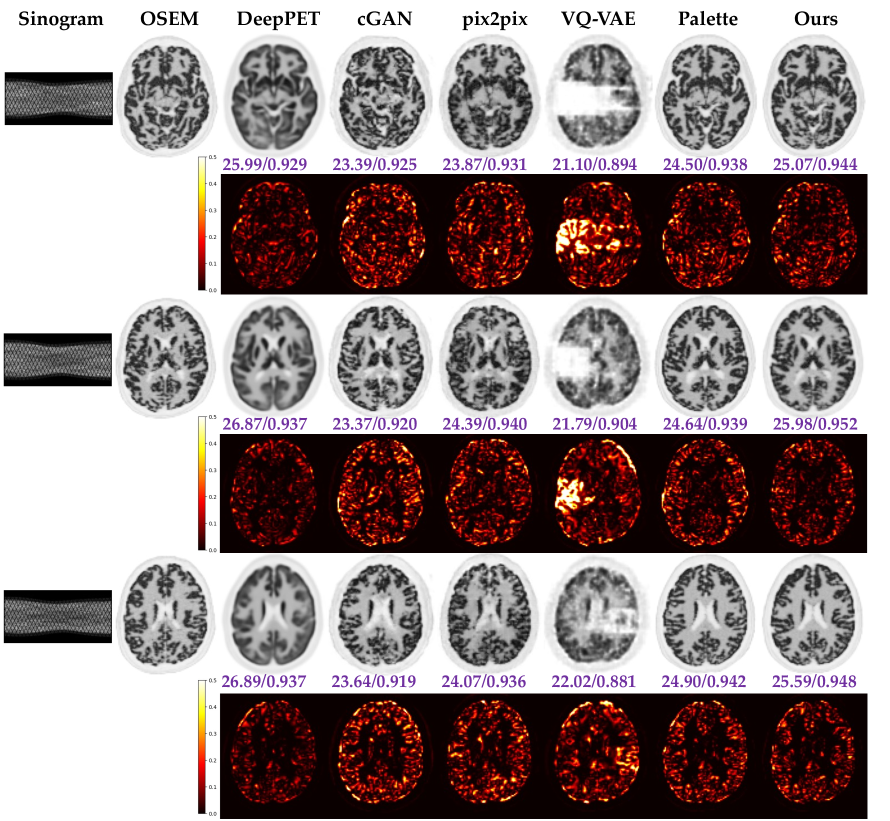

Fig. 1: Qualitative comparison of PMDM-PET with Five Baselines on Three Example Slices. The first column shows the input sinogram images, and the second column shows the reference images reconstructed using OSEM algorithm. The third to seventh columns correspond to the five baselines (labeled above each image), and the final column shows the reconstructed PET images using our proposed PMDM-PET method. PSNR/SSIM values are reported below each slice, and squared error maps between each method and the reference image are also displayed (second, fourth and sixth rows).

We compared the performance of PMDM-PET against five baseline algorithms: DeepPET [haggstrom2019deeppet], cGAN [mirza2014conditional], pix2pix [isola2017image], VQ-VAE [van2017neural], and Palette [saharia2022palette]. It is worth noting that DeepPET can be regarded as a model trained without a perceptual constraint and Palette is trained without an MSE estimator, which can also be seen as an ablation study when compared to our PMDM-PET. Table. 1 summarizes the average pixel-wise PSNR (dB)/SSIM/NRMSE values across all reconstructed slices, along with the number of trainable parameters for each method. PMDM-PET achieves a 0.61 dB improvement in PSNR over Palette, demonstrating the effectiveness of incorporating an MMSE estimator to reduce distortion while preserving high perceptual quality. While DeepPET achieves comparable PSNR values, its reconstructed PET images appear significantly blurrier and less perceptually faithful, as illustrated in Fig. 1. This aligns with the tradeoff theory discussed in Sec. 2.1, where generative models leveraging stochastic posterior sampling sacrifice pixel-wise distortion (resulting in lower PSNR) while maintaining fidelity to the underlying distribution [blau2018perception]. Additionally, PMDM-PET outperforms cGAN, pix2pix, and VQ-VAE by approximately 3.81 dB, 3.58 dB, and 5.15 dB in PSNR, respectively. Fig. 1 further visualizes reconstruction results, comparing all baseline methods side by side. PMDM-PET produces the most robust reconstructions, excelling in both distortion and perceptual quality. In contrast, cGAN, pix2pix, VQ-VAE, and Palette introduce noticeable artifacts, while DeepPET generates overly smooth reconstructions with unrealistic fine details.